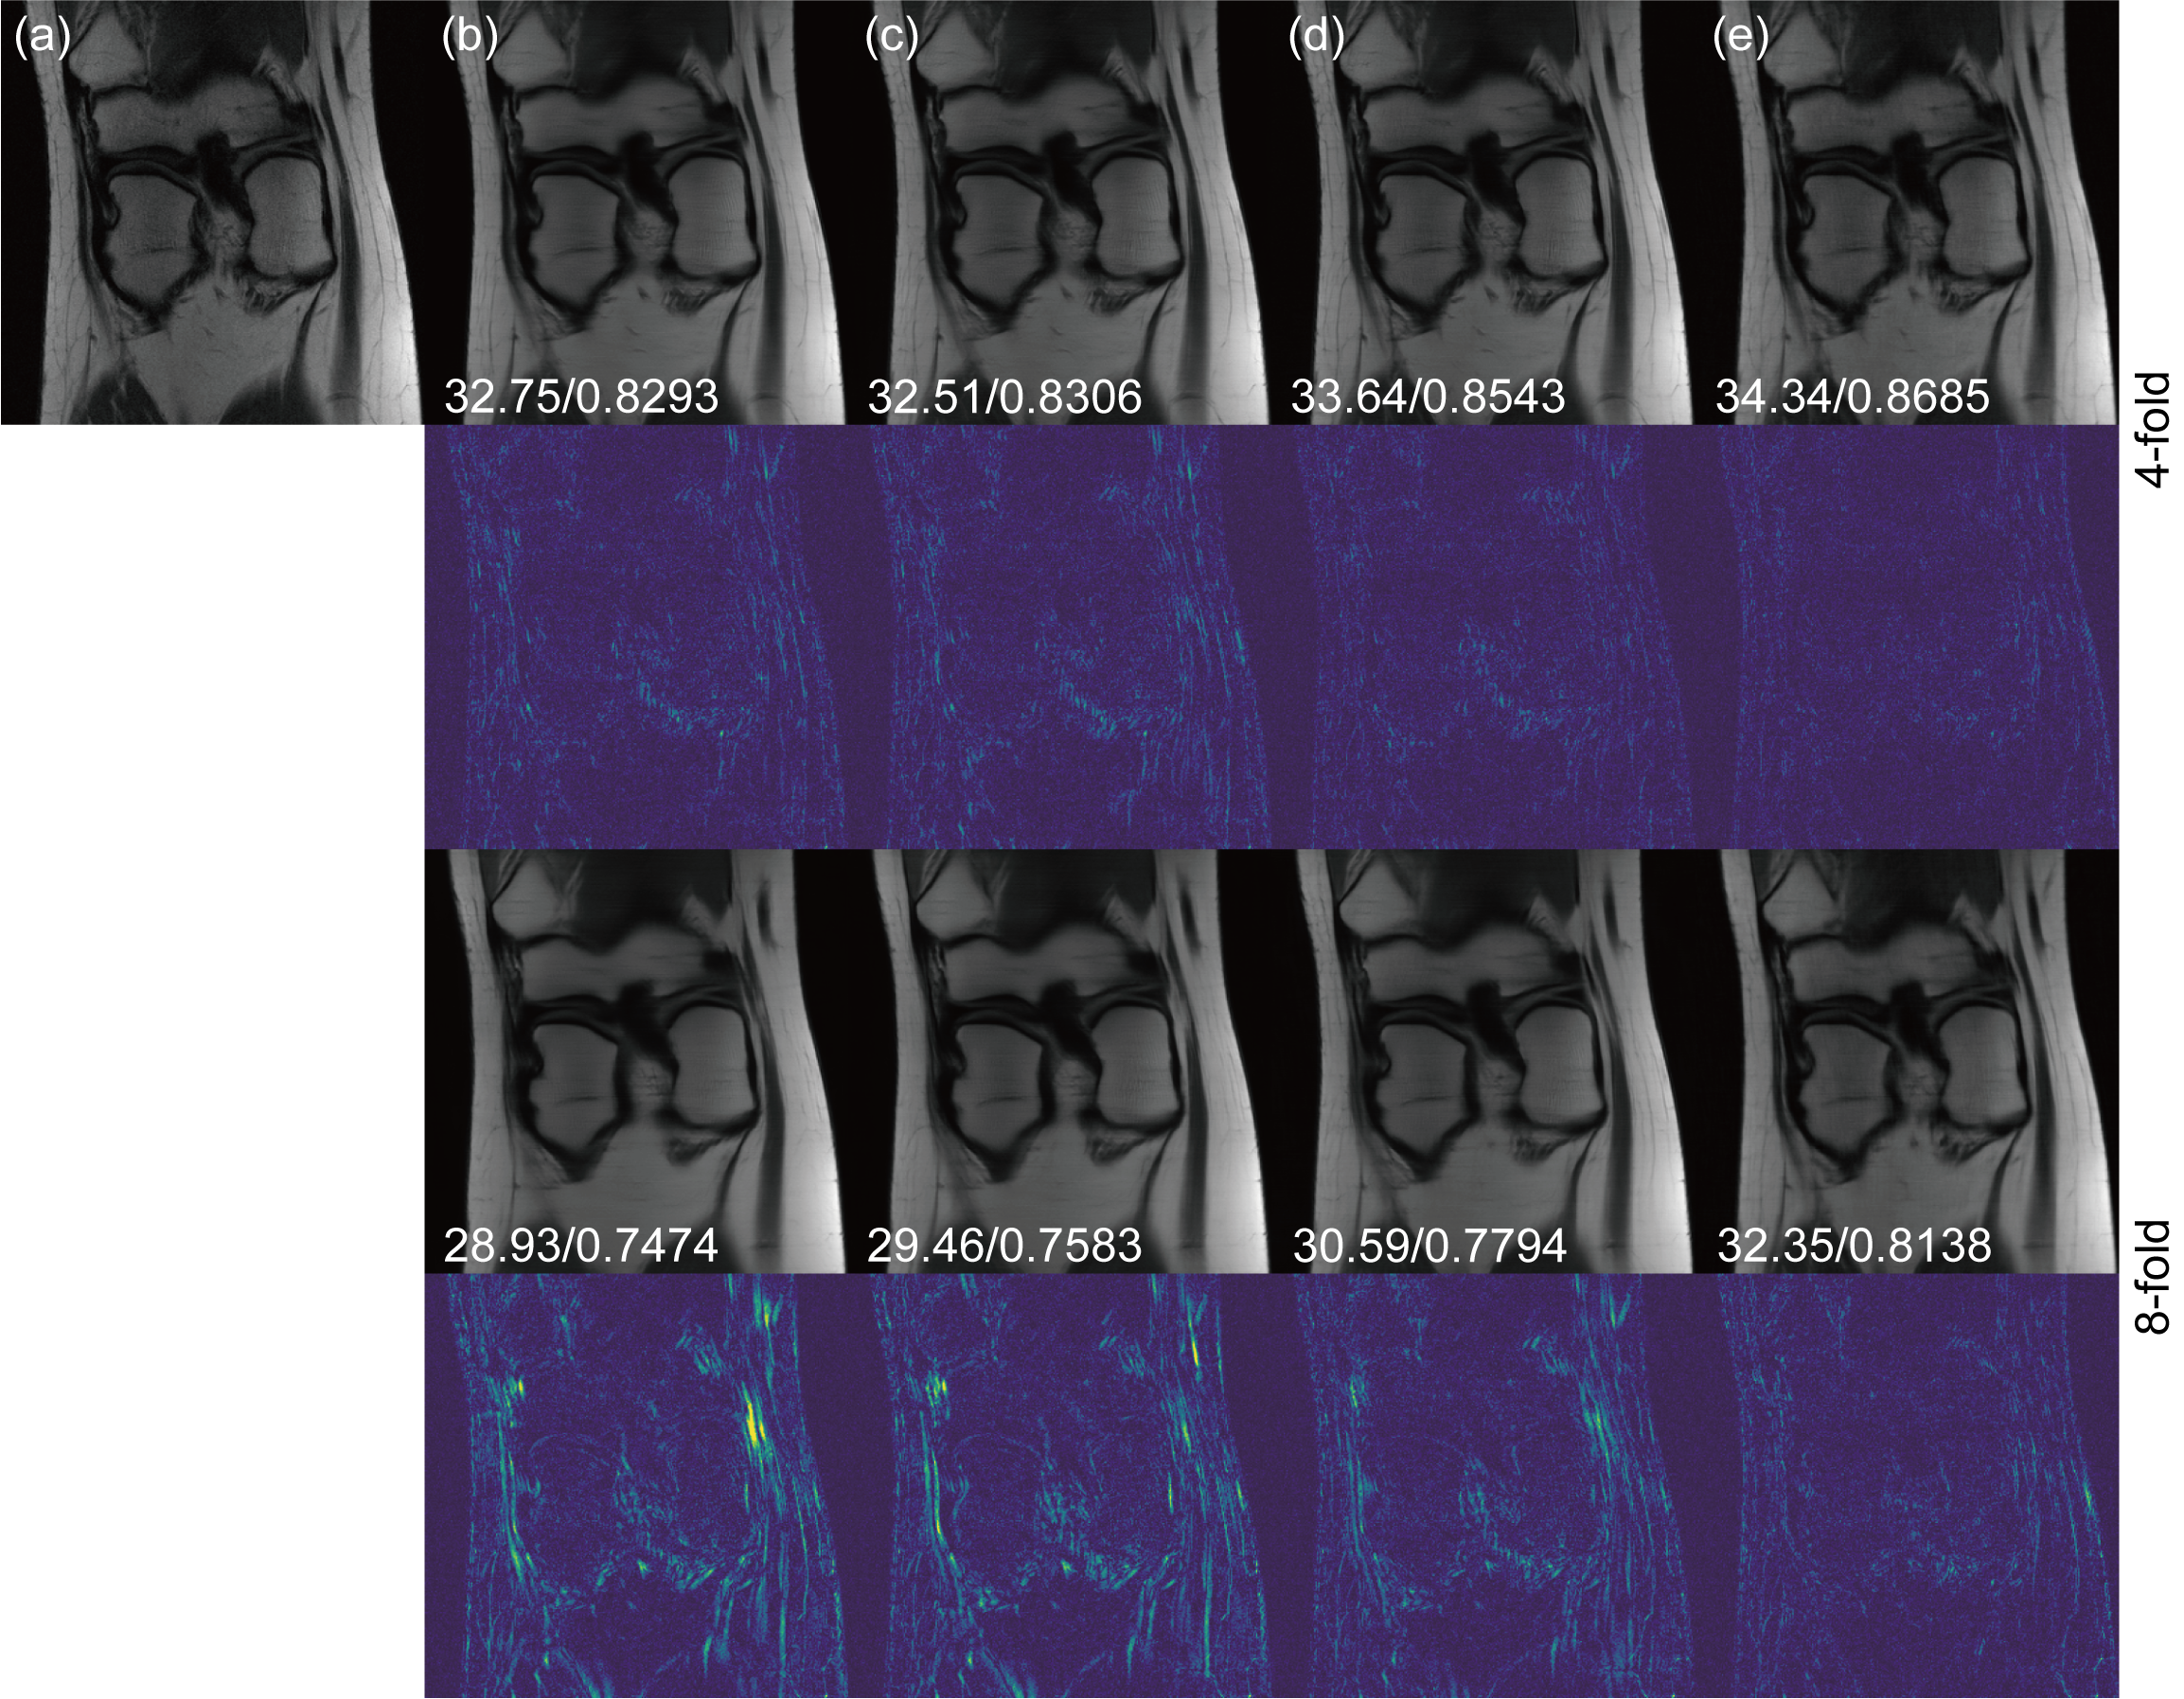

Fig. 3 demonstrates reconstruction results for 4-fold and 8-fold Cartesian under-sampling masks. We compare our k-space cold diffusion model with U-Net, W-Net and E2E-VarNet. Corresponding error maps are shown under each reconstruction image. All error maps have been magnified five times for better demonstration. We find that our k-space cold diffusion model preserves more image details and leads to cleaner error maps compared to other models. Tab. 1 provides evaluation metrics for the 4-fold and 8-fold Cartesian under-sampling reconstructions, showing that our model outperforms others with a PSNR/SSIM of 30.58/0.7150 for 4-fold and 29.51/0.6414 for 8-fold. In Fig. 4 and Tab. 2, we demonstrate reconstruction results and evaluation metrics for Gaussian sampling masks with 4-fold and 8-fold acceleration tasks. Our method outperforms others with a PSNR/SSIM of 30.31/0.7059 and 29.59/0.6416 for 4-fold and 8-fold, respectively. Similar to the Cartesian sampling reconstruction tasks, we found our model preserves more image details and textures and gives out cleaner error maps.